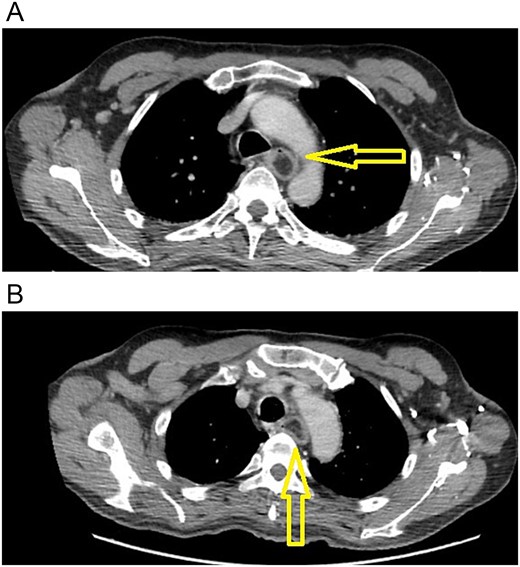

Case report

The patient is a 70-year-old male with a past medical history of prostate cancer. He presented with a two-year history of progressive dysphagia. At first, he complained of epigastric pain, nausea, and vomits. In the last three months, he found it increasingly difficult to eat anything solid, until he found it impossible to swallow. Due to this, an upper endoscopy and a contrast-enhanced chest computed tomography (CT) were done at that time, revealing a giant superior esophageal polyp (Fig. 1) 28 cm away from the dental arcade; therefore, surgical resection was recommended. Nonetheless, the patient refused any surgical management.

(A) CT scan: esophageal polyp is seen in the esophageal lumen. (B) CT scan: esophageal polyp completely obstructs but does not invade the esophagus.